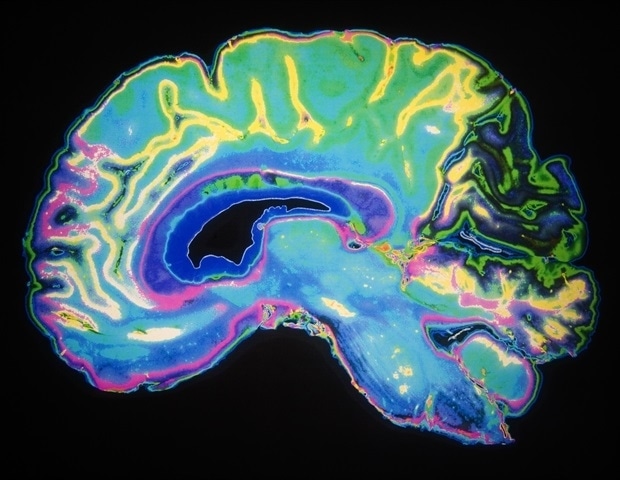

Микропластик может способствовать развитию нейродегенеративных заболеваний, таких как болезнь Альцгеймера и Паркинсона. Новое исследование выявило пять способов, которыми микропластик может вызвать воспаление и повреждение головного мозга.

Исследователи выделили пять основных путей, посредством которых микропластик может нанести вред мозгу, в том числе активировать активность иммунных клеток, генерировать окислительный стресс, разрушать гематоэнцефалический барьер, повреждать митохондрии и повреждать нейроны.